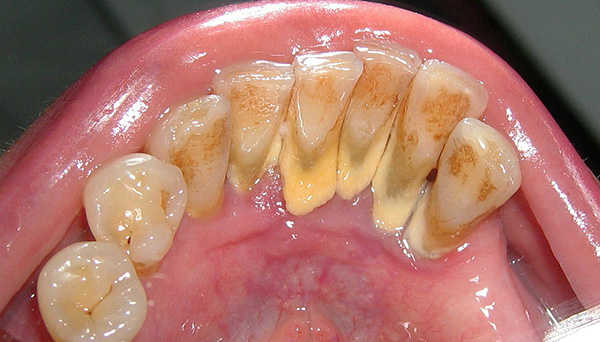

- trattamento dei denti in cattive condizioni (i denti "marci" sono terreno fertile per i batteri e comportano rischi per il corretto innesto di impianti);

- igiene professionale (rimozione di placca e pietra).

Un'igiene orale inadeguata può portare all'infiammazione dei tessuti attorno all'impianto e alla sua conseguente rifiuto. Per questo motivo, si consiglia al paziente di rafforzare le procedure igieniche almeno 2-3 settimane prima del posizionamento dell'impianto.